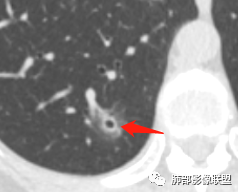

连续层面显示这个应该是空泡,或者小空洞,远端没有,近端也没有,周围环形软组织增厚。而空泡,影像上只是根据5mm界线,病理上不一定。

问一个问题,肺动脉肺静脉?为啥?

静脉,夹角90,周边没气管伴行。

静脉吧,动脉同时会伴有一根气管

这些呢?为啥?

动脉,有支气管伴行

伴有支气管

南边:

假如这是含气支气管,伴随的哪条动脉呢?近端从哪来?为啥环形壁增厚而又不均匀?都不太符合,所以支持空泡或小空洞。

上次刘纯老师提出,空泡征是一个影像征象,不是一个病理征象,我比较支持,他就是一个影像上的小低密度腔,原因很多,但是影像上与小的空洞表现区分不了。其中的原理:有一条是内容物排出后的残腔,其实也是空洞的原理。